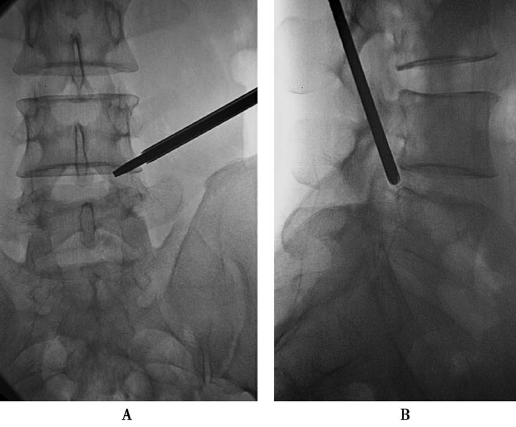

上关节突尖的稍背侧(图11):0.5%利多卡因局麻后用勺状针由穿刺点与额状面呈20°缓缓进针,边进针边注入局麻药,达上关节突尖的稍背侧,抵骨,注入局麻药10ml。

图11 勺状针针尖抵达上关节突尖的稍背侧A.前后位透视;B.侧位透视

上关节突尖的腹侧(图12):调整勺状针的勺状面向腹侧,稍加大穿刺角度,使针尖略向腹侧进针,滑过上关节突尖部进入椎间孔,注入局麻药3ml。

图12勺状针针尖抵达上关节突尖的腹侧A.前后位透视;B.侧位透视

1.穿刺时,勺状针头位置受上关节突尖的干扰稍靠头端,要注意出口神经根的保护(图11);应用双针技术是合适的(图13)。